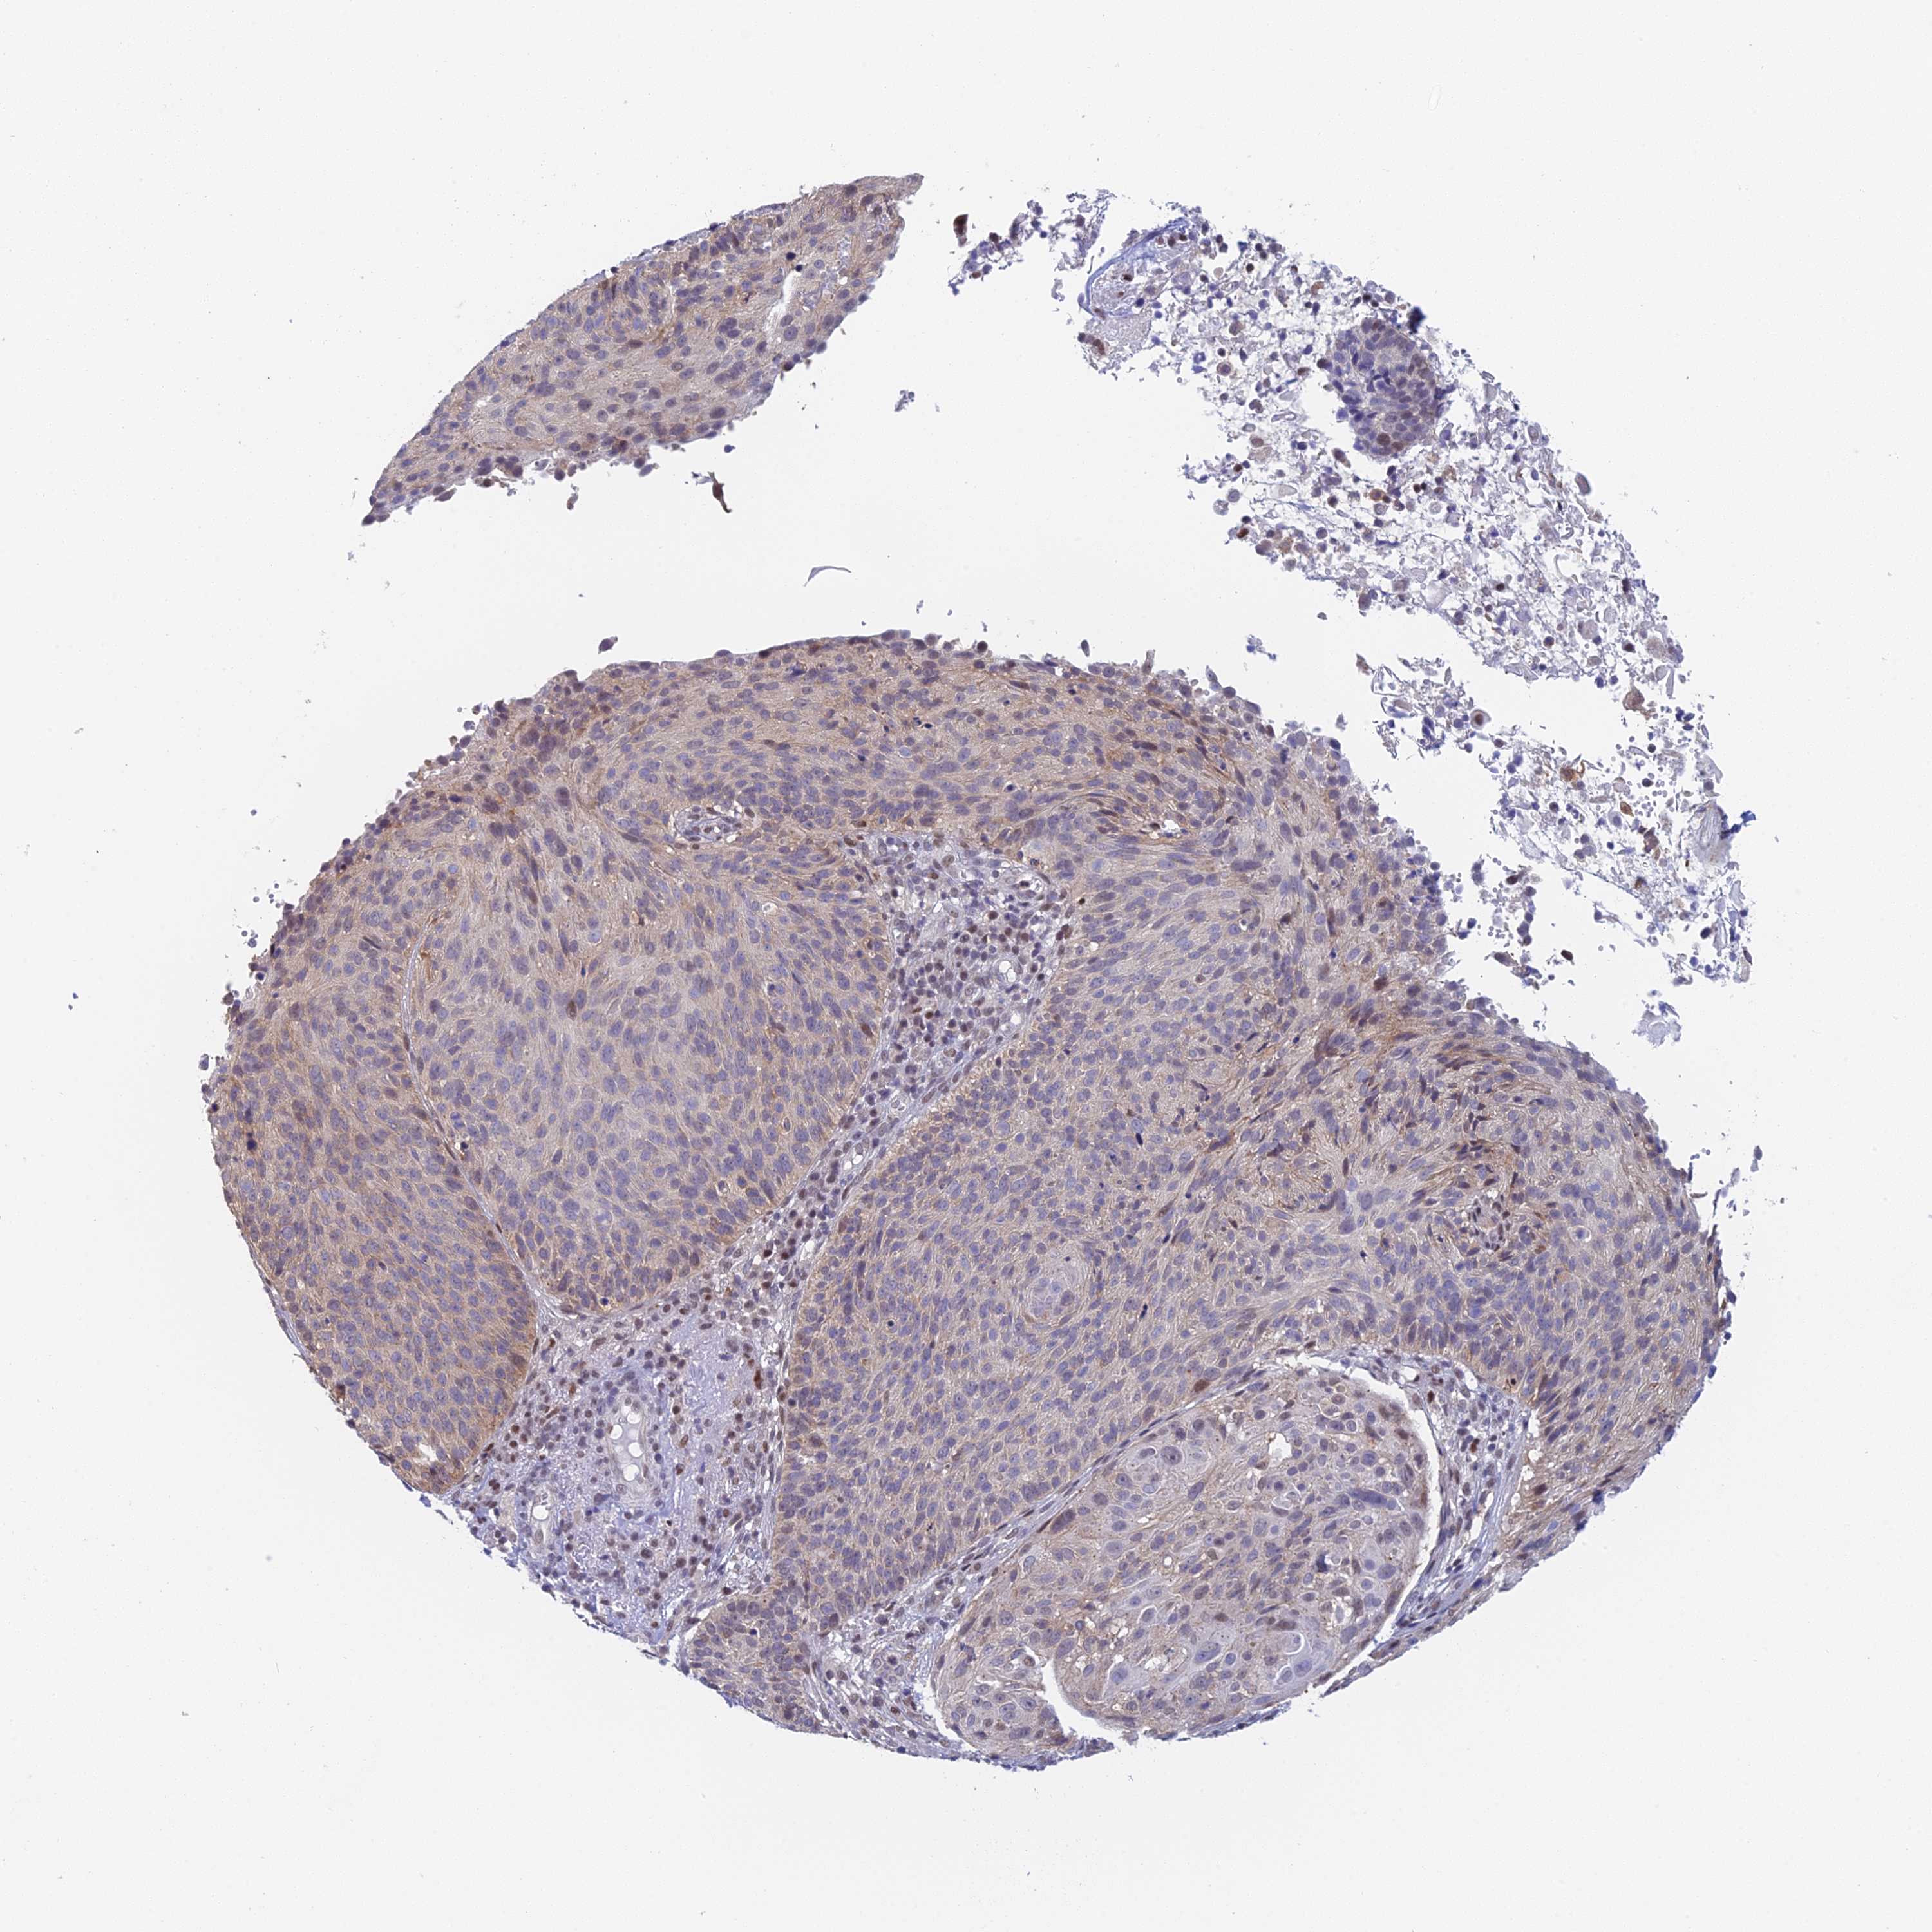

CERVICAL CANCER - Protein expressioni

A mouse-over function shows sample information and annotation data. Click on an image to view it in a full screen mode. Samples can be filtered based on level of antibody staining by selecting one or several of the following categories: high, medium, low and not detected. The assay and annotation is described here.

Note that samples used for immunohistochemistry by the Human Protein Atlas do not correspond to samples in the TCGA dataset.

Antibody stainingi

Antibody staining in the annotated cell types in the current human tissue is reported as not detected, low, medium, or high, based on conventional immunohistochemistry profiling in selected tissues. This score is based on the combination of the staining intensity and fraction of stained cells.

Each image is clickable and will lead to virtual microscopy that enables deeper exploration of all samples and also displays staining intensity scores, fraction scores and subcellular localization as well as patient and tissue information for each sample.

Antibody HPA043666

Antibody HPA050552

Staining

High

Medium

Low

Not detected

Intensity

Strong

Moderate

Weak

Negative

Quantity

>75%

75%-25%

<25%

None

Location

Nuclear

Cytoplasmic/membranous

Cytoplasmic/membranous,nuclear

Squamous cell carcinoma, NOS

Adenocarcinoma, NOS